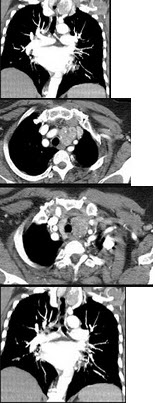

40岁,女,发现颈部肿块,随吞咽上下移动,触之无搏动,咳嗽、气喘一周,请结合CT检查选择最可能的诊断( )

A:胸腺瘤

B:胸内甲状腺瘤

C:无名动脉瘤

D:无名动脉伸展扭曲

E:淋巴瘤